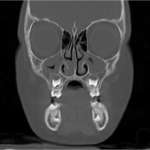

Progetto digitale full-arch eseguito con chirurgie multiple Free

In questo articolo viene presentato un metodo che ha previsto l’utilizzo della tecnologia digitale per eseguire una riabilitazione full-arch in tempi differiti. La raccolta dei dati in formato digitale e le immagini di radiologia 3D hanno consentito di sviluppare un’unica, completa pianificazione delle procedure per affrontare un caso complesso attraverso più interventi chirurgici e protesici in momenti diversi;